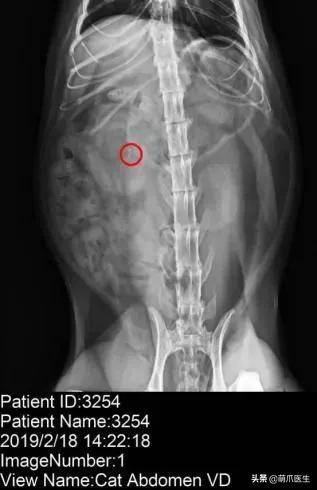

肾脏结石(X线片)